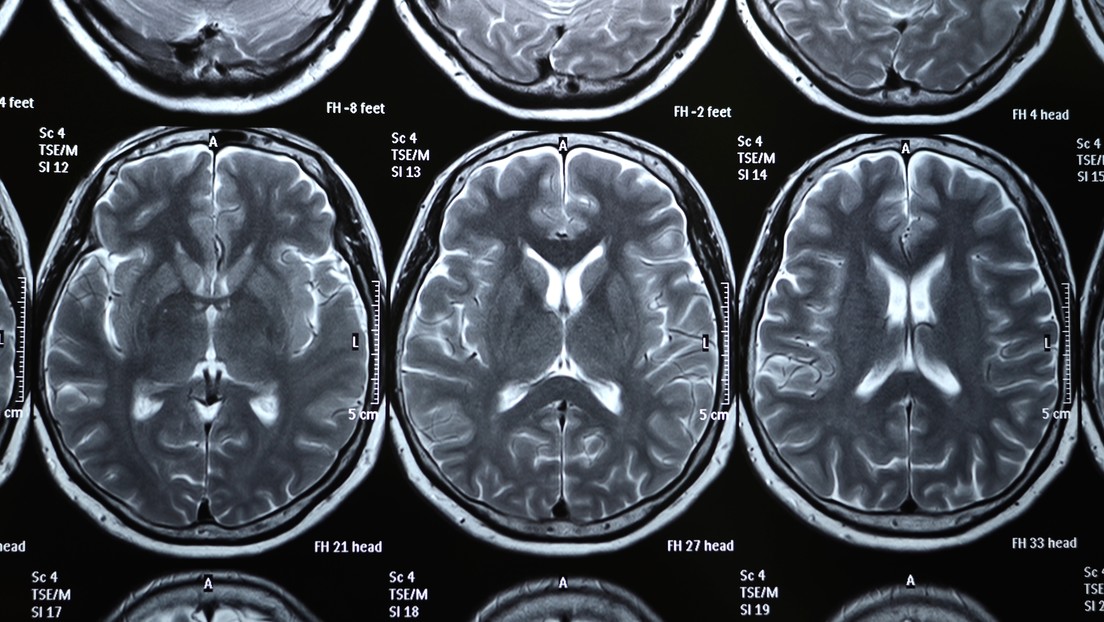

Especialistas de la Universidad de Oxford han identificado la pérdida "significativa" de materia gris en regiones del cerebro relacionadas con el olfato y el gusto en los pacientes que padecieron incluso una forma leve de coronavirus, según concluyen en un nuevo estudio publicado en medRxiv que aún no ha sido evaluado por pares.

El análisis de los datos del grupo que padeció covid-19 en algún momento mostró una pérdida "significativa" de materia gris en regiones del cerebro relacionadas con el olfato y el gusto: el giro parahipocampal izquierdo, la corteza orbitofrontal izquierda y la ínsula izquierda. Estos cambios no se observaron en el grupo que no se infectaron.